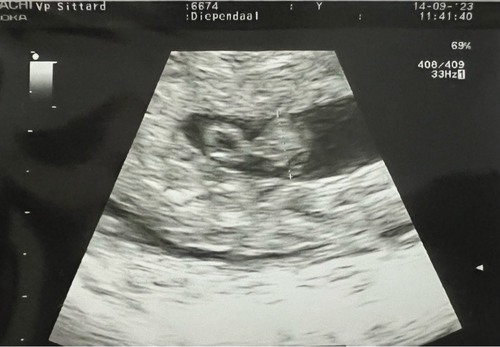

Ik heb vandaag de eerste echo gehad, volgens mijn berekening zou ik ongeveer 6+0 moeten zijn maar het was moeilijk te schatten door een late ovulatie en ook hebben we in juni een missed abortion gehad.. maar door de echo schatten ze me 5+4 en we hebben ook al een kloppend hartje gezien, wat een opluchting!

Ik heb met 6 weken en 2 dagen een (nog traag) kloppend hartje gezien! Vandaag weer een echo gehad met 6 weken en 5 dagen en de groei is verdubbeld en het hartje ging goed tekeer!